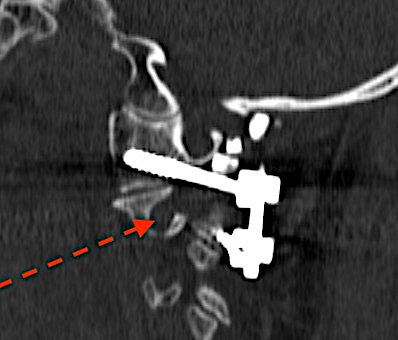

Fractura de odontoides de >3 meses de evolución. Obsérvese el remodelado óseo presente típico: bordes redondeados, esclerosis…

TC sagital control al año de la intervención. Paciente asintomático.

Reconstrucción coronal TC cervical 1 año.